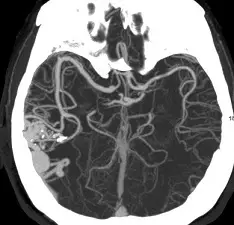

頭部 CTA的影像如下圖,下列何者為最適當之診斷?

本題測驗對於頭部電腦斷層血管攝影 (CTA, Computed Tomography Angiography) 影像中常見腦血管疾病的辨識能力。動靜脈畸形 (Arteriovenous Malformation, AVM) 是一種先天性的血管發育異常,其特徵為動脈與靜脈之間缺乏微血管網的緩衝,血液直接由動脈流入靜脈,形成一團異常糾結的血管叢,稱為血管畸形團 (Nidus)。

本題提供的影像為頭部 CTA 的軸切面 (Axial view) 最大強度投影 (Maximum Intensity Projection, MIP) 重組影像。 在影像中大腦右半球(畫面左側)的皮質至皮質下區域,可以明顯觀察到以下特徵:

- 血管畸形團 (Nidus):存在一團極度糾結、擴張且不規則的異常血管網,呈現典型的「成團蠕蟲狀 (bag of worms)」外觀。

- 供血動脈 (Feeding arteries):可見來自大腦中動脈 (MCA) 系統的分支異常粗大,並直接匯入該血管團中。

- 引流靜脈 (Draining veins):在血管團周邊可見明顯擴張的靜脈結構,將血液提早引流而出。